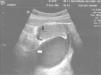

Ecograficamente, foi possível confirmar a ocorrência de distensão vaginal preenchida por conteúdo hipoecogénico (colpometra) e um hematometra laminar (fig. 3). Ambos os ovários eram normais. Analiticamente sem alterações de relevância; sedimento urinário e função renal normais.

Figure 3.

Ecografia pélvica (seta branca: dilatação da vagina, hematocolpos; seta preta: hematometra).